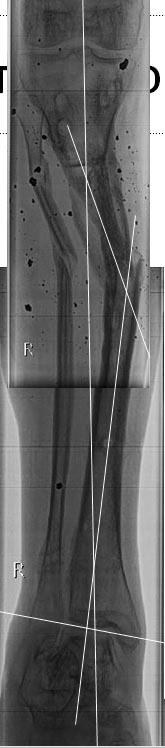

Как лучше устранить деформацию обеих голеней. Уважаемые коллеги на лечение спустя 10 мес. после травмы поступил 35 летний пациент. Изначально лечился в аппаратах. Длительно, в выписке описываются инфекционные осложнения. В настоящее время аппараты демонтированы, ран на правой и левой голени нет. Слева планируем устранить в один прием с фиксацией стержнем. Справа - мнения разошлись: от тоже стержнем, до остеотомии в нижней трети (вне перелома) с коррекцией механической оси. Прошу поделиться мнениями и опытом. Спасибо!

Стоило бы поподробнее представить свой план коррекции, скиаграммы, и потом задавать более конкретные вопросы.

Как именно на левой голени планируете коррекцию? Где чего пересекать-разъединять?